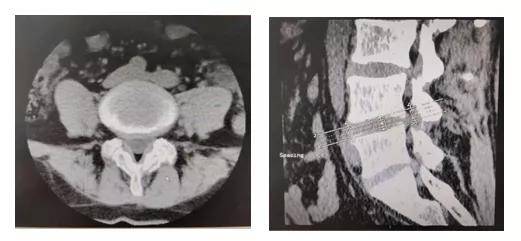

CT检查

CT检查密度分辨率高 , 无影像重叠 , 易于发现微细骨质破坏 , 对影像重叠或解剖结构复杂部位的显示优于常规X线平片 。 CT平扫可以清楚显示椎间盘突出的部位、大小、形态和神经根、硬脊膜受压的情况 , 同时还可显示黄韧带肥厚、小关节增生、椎管和侧隐窝狭窄等情况 。 突出的椎间盘有无钙化 , 一般也需要CT检查明确 。

文章图片